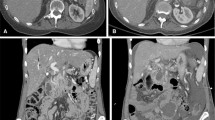

CeCT imaging

Differences between attenuation pre- and post-IRE in the arterial and portal venous phase were not statistically significant. Table 4 and Fig. 3 show the tumour and ablation zone attenuation characteristics on ceCT. Interobserver agreement was mostly substantial to excellent (Table 3). Compared to the healthy pancreatic parenchyma the initial tumour appeared either isodense (56 %) or hypodense in the arterial phase (44 %) and hypodense (72 %) in the portal venous phase. Immediately after IRE, intralesional and periablational gas pockets were present in all cases. Post-IRE the ablation zones were primarily hypodense in the arterial phase after 6 weeks and 3 and 6 months (80 %, 52 %, and 56 %, respectively). In the portal venous phase 76 % of the ablated areas were slightly hypodense immediately post-IRE; at 6 weeks and 3- and 6-month follow-up, ablation zones were hypodense in 92 %, 92 %, and 94 %, respectively.

Imaging findings during follow-up on ceCT (a) Isoattenuating tumour on ceCT pre-IRE (b) CT-guided placement of electrodes around the outer border of the tumour (c) Confirmation of correct electrode configuration according to the treatment plan with a nonenhanced CT scan (d) Hypoattenuating IRE ablation zone with intralesional gas pockets immediately after IRE (e) Hypoattenuating IRE ablation zone at 6 weeks of follow-up (f) Hypoattenuating IRE ablation zone at 3 months of follow-up